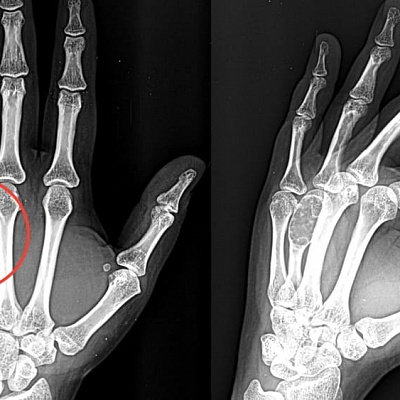

Особняком стоят костные опухоли. Часто встречаются остеомы, доброкачественные костные опухоли. Чаще всего они медленно растут и обычно не вызывают симптомов. Остеомы могут быть обнаружены случайно при рентгенологическом исследовании. Другой вариант — остеоид-остеомы: небольшие доброкачественные опухоли кости, часто характеризуется ночными болями, которые эффективно снимаются нестероидными противовоспалительными препаратами. Наконец, встречаются остеобластомы, доброкачественные опухоли, похожие на остеоид-остеомы, но значительно большего размера. Они вызывают боли и иногда приводят к патологическим переломам. Остеобластомы встречаются реже и ведут себя агрессивнее. Все новообразования так или иначе требуют лечения.

- рентгенография;

- Очкуренко А.А., Молов Х.Х. Локализация доброкачественных опухолей, опухолеподобных и воспалительных заболеваний в костях кисти. Медицина Кыргызстана. №3. 2012 г. 182-183 с.

- Котельников Г.П., Колсанов А.В., Николаенко А.Н., Попов Н.В., Щербовских А.Е., Иванов В.В., Приходько С.А., Платонов П.В. Хирургическое лечение доброкачественных опухолей и опухолеподобных заболеваний костей кисти. Хирургия. Журнал им. Н.И. Пирогова. 2018;(1):86‑89.